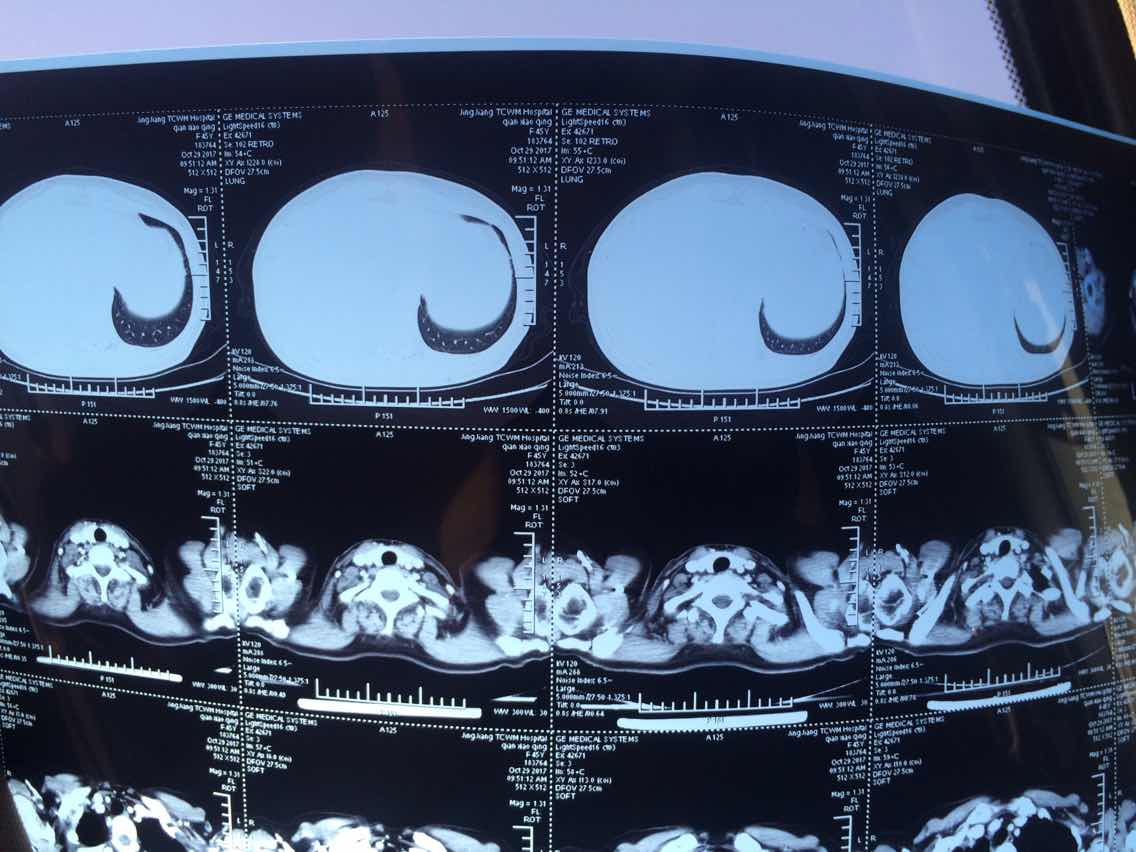

2017.8.25

2

3